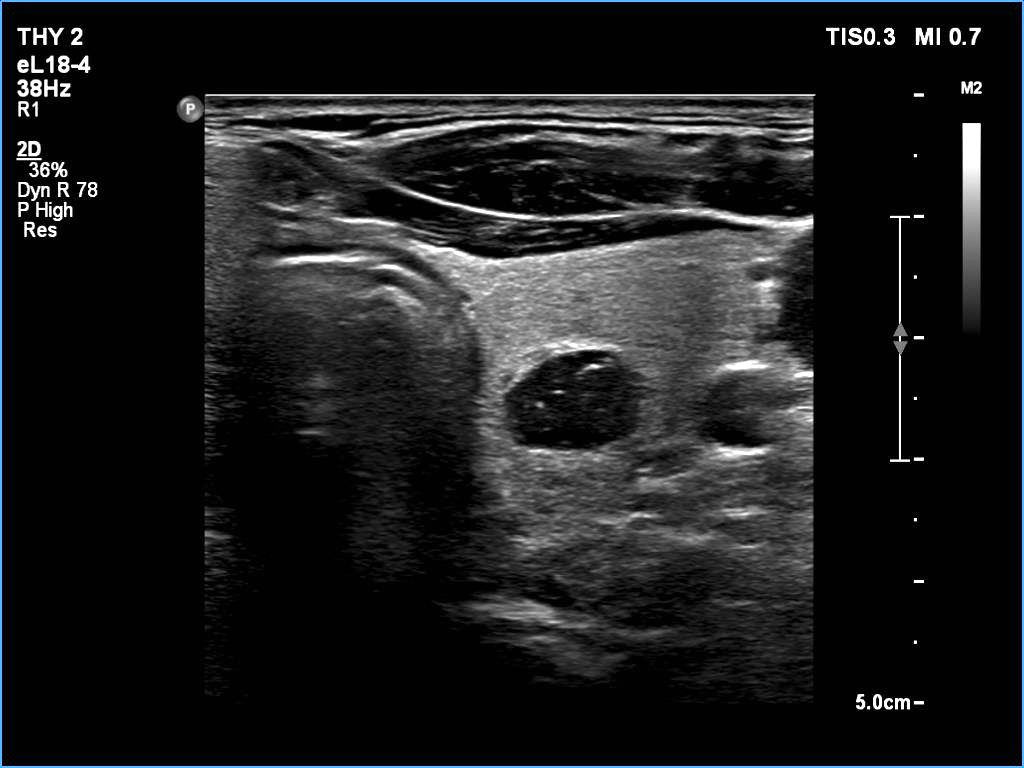

Ultrasonography: The thyroid was echonormal. There was a larger nodular mass in the right lobe which was composed of a dominantly solid echonormal portion that surrounded a dominantly cystic area. There were multiple nodules in the left lobe. The latter included an almost completely cystic lesion.

Comment. The right nodule is dominantly solid one because the cystic portion is less than 50%. The cystic portion of the nodule is multichambered which presents spongiform areas. The left cystic nodule is an almost completely cystic lesion, that has disappeared after the removal of cystic fluid.